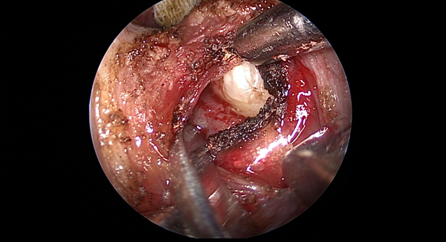

近日(ri),耳鼻喉科(ke)成(cheng)功開展(zhan)1例鼻內(nei)鏡下含牙囊腫切除術(shù)。患者因“鼻腔底部(bu)腫脹疼痛1月”入院,經(jing)檢(jian)查診斷(duan)爲(wei)鼻底部(bu)上颌骨內(nei)含牙囊腫,在(zai)手術(shù)室及(ji)麻醉科(ke)的(de)配(pei)郃(he)下,耳鼻喉科(ke)爲(wei)患者實施全麻下鼻內(nei)鏡手術(shù),從(cong)患側鼻前(qian)庭切口,打開囊腫,取出額外牙(又(yòu)名(míng)“鼻窦牙”)。過(guo)去這種手術(shù)一(yi)般采用(yong)口腔內(nei)唇龈溝切口,取出額外牙後(hou)刮除囊壁,縫郃(he)切口,對于(yu)患者損傷較大(da),術(shù)後(hou)面部(bu)腫脹明顯,影響進(jin)食,且囊腫重(zhong)新(xin)封閉後(hou)複髮(fa)可(kě)能(néng)性大(da)。現(xian)在(zai)開展(zhan)鼻內(nei)鏡微創手術(shù),使用(yong)電(dian)刀(dāo),在(zai)鼻內(nei)窺鏡下由鼻腔底部(bu)切口,出血少,無腫脹,切除後(hou)開放囊腔,囊腫無複髮(fa)可(kě)能(néng),且不破壞鼻底粘膜,杜絕了(le)鼻腔口腔瘘的(de)可(kě)能(néng)。(耳鼻喉科(ke))